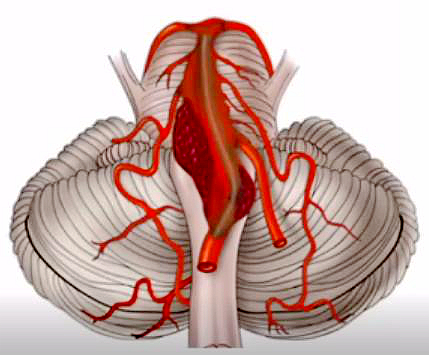

椎-基底动脉冗长扩张症示意图

椎-基底动脉冗长扩张症(VBD)是一种以椎动脉基底动脉异常扩张、延长和扭曲为特征的动脉病变。部分VBD患者无临床症状,不少人是头部血管成像检查后发现,也有一部分患者出现面肌痉挛、三叉神经痛、脑干压迫症状、头晕甚至昏迷等,部分症状一旦产生,将会明显影响生活质量甚至致死致残。据流行病学调查,所有人群中VBD的患病率为0.2%-4.4%,脑卒中人群中VBD患病率为2.6%-17.1%,而VBD伴急性闭塞的患者较为罕见。该类疾病是在椎-基底动脉冗长扩张基础上并发的急性闭塞,救治难度大,风险极高。